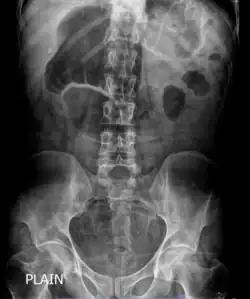

X-ray showing distended stomach and bowel loops. Dilated bowel loops are a characteristic of chronic intestinal pseudo-obstruction.

The diagnosis of CIPO is mostly clinical, backed by radiographic documentation of dilated bowel with air-fluid level after exclusion of organic lesions obstructing the gut lumen, as determined by radiologic and/or endoscopic examinations. Thus, diagnostic investigations in patients with suspected CIPO are required to rule out mechanical blockage, identify possible sources of secondary forms, investigate underlying pathophysiological mechanisms, and reveal potential consequences.[24]

In order to look into possible intestinal obstruction, radiologic examinations are essential. Simple and cheap to perform, plain film x-rays can show the traditional indicator of air-fluid levels and dilated bowel loops, which is best seen in the erect film.[25] Abdominal x-rays, however, are unable to definitively differentiate between genuine mechanical intestinal obstruction and pseudo-obstruction.[26] Afterwards, additional information is obtained by abdominal computed tomography (CT) imaging in order to rule out an extraluminal, gut wall, or intraluminal mechanically obstructive lesion.[25]